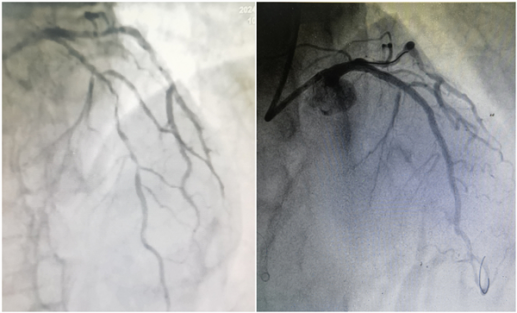

术前前降支血管严重狭窄(左) 术后管腔内无狭窄,恢复血流通畅(右)

急诊冠脉造影检查显示,周爹爹的三根冠脉血管都发生了严重狭窄,导致心脏严重供血不足,紧急实施心脏支架手术恢复右冠状动脉供血,医生建议休养一段时间后再择期处理左边冠状动脉狭窄病变。出院后的周爹爹尽管一直在规律服药,但胸闷问题仍不时发作。

“本来还想再观望一段时间,现在看来不处理不行了。”4月15日,苦不堪言的他求诊武汉亚洲心脏病医院。进一步检查发现,周爹爹的左前降支严重狭窄伴弥漫性重度钙化,整个钙化病变节段血管丧失了动脉应有的弹性,犹如长出了一块块的“石头”,同时存在钙化结节情况,严重阻挡着血管里血液的正常流动。

4月16日晚上,鄢华院长、熊岗主任带领手术团队,在血管内超声的帮助下精准确认了周爹爹钙化病变的位置、大小和程度,首先通过高速旋转带有钻石颗粒的旋磨头,将病变处磨出了一条通道;随后通过振波球囊对深层钙化进行处理,充分地碎裂周爹爹血管内的“石头”, 将布满“拦路石”的钙化病变血管修复得“光滑如新”;最后在前降支血管植入支架,完成了血运重建,成功打通了“生命线”。术后的周爹爹恢复情况良好,已于4月19日康复出院。